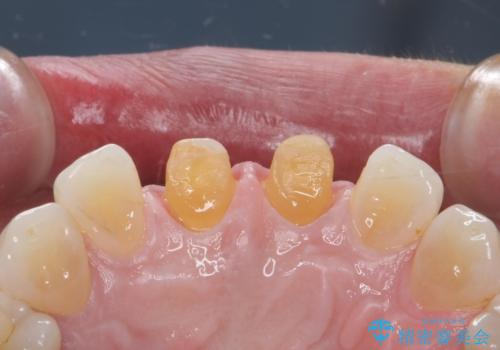

- 前歯につけていたべニアが取れたとのことで来院された患者様です。

より脱離リスクの低いクラウンでの修復を行います。

取れていない方のべニアも周囲の歯と色調が合っていなかったため、一緒にやり替えました。